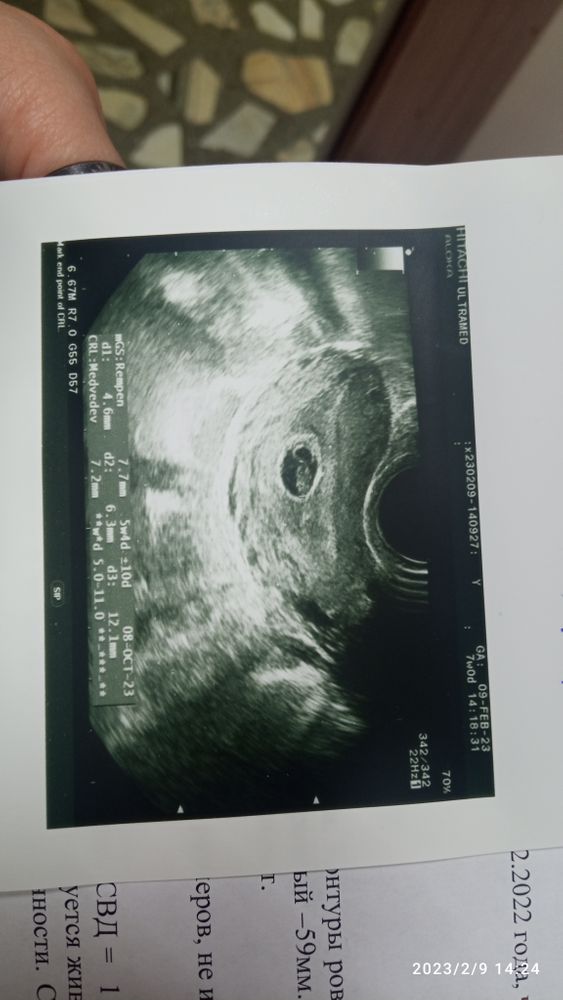

Первое УЗИ

Какое чудо 😍😍😍 ну такой человечек уже !))

Какая прелесть ☺️